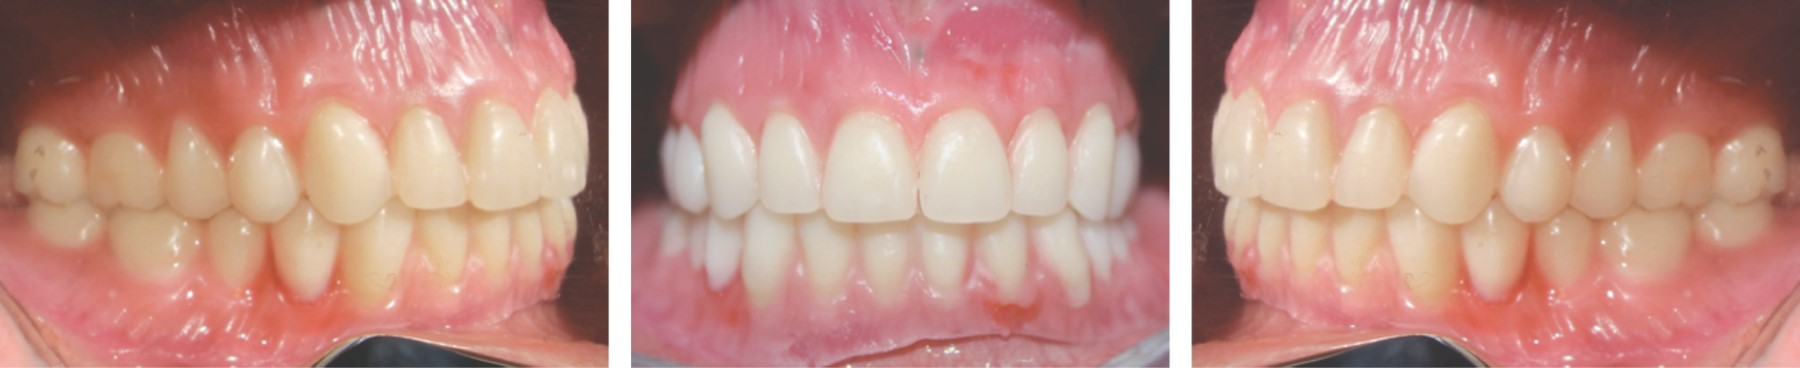

En el procesado de las prótesis se realizó un caracterizado intrínseco con Opti-Cryl (Figura 18) y por último se colocaron las prótesis y se rectificó la oclusión bibalanceada en movimientos excéntricos (Figura 19). Los controles de ambas prótesis totales se hicieron tres días después de la colocación, a la primera y tercera semana, y luego cada tres meses.

En las siguientes imágenes se muestran las fotos intraorales y extraorales comparativas en la transición del tratamiento integral (Figuras 20 y 21).